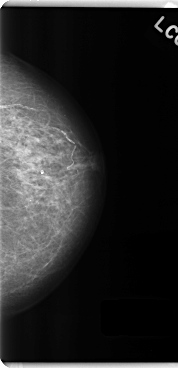

C_0195_1.LEFT_CC

LEFT_CC LINES 4784 PIXELS_PER_LINE 2312 BITS_PER_PIXEL 12 RESOLUTION 50 NON_OVERLAY